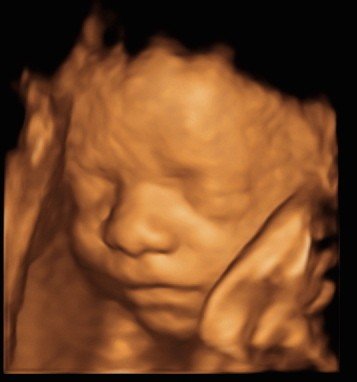

View beautiful baby scan images captured in our studios

Baby scan image 1